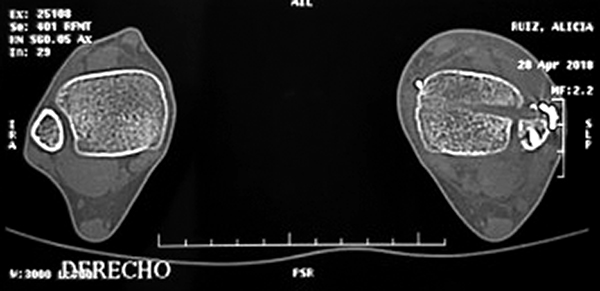

Las radiografías preoperatorias fueron realizadas para medir: espacio tibio-peróneo o Tibiofibular Clear Space (TCS), el espacio de superposición tibio-peróneo o tibiofibular overlap (TFO); todos estos parámetros para diagnosticar la lesión sindesmal. La TAC comparativa de tobillos con cortes axiales a 1 cm de la articulación, permite realizar el diagnóstico, si existiese una diferencia mayor a 2 mm de desplazamiento tibio-peróneo entre ambas articulaciones. Estos estudios en el postoperatorio inmediato permiten constatar la reducción de la articulación tratada.3

Se observó una reducción aceptable (radiográfica y tomográficamente) en el postoperatorio inmediato en 20 pacientes (fig. 6). Un caso presento una distancia de 3mm comparado con el contralateral, no detectado con radioscopia sino tomográficamente y no requirió ningún tipo de tratamiento diferenciado. La comparación de la proporción encontrada contra el valor teórico elegido (25%) fue estadísticamente significativa (Z=-2,1418; p=0,0322).

Figura 6: Tomografía comparativa de ambos tobillos, corte axial a 2 cm de la articulación con reducción aceptable.